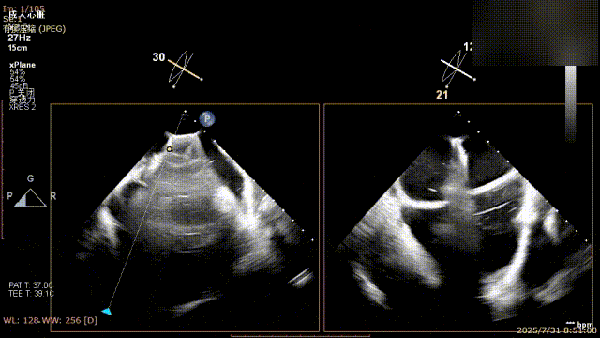

手术过程中,麻醉与围术期医学科副主任医师马金本确保麻醉过程平稳。心脏大血管外科主治医师董明亮穿刺股静脉置入血管鞘,并在心脏超声科梁皓主任及段福建教授TEE引导下,顺利穿刺房间隔,房间隔穿刺高度4.9cm。随后,在王安彪主任以及刘洋教授指导、心脏超声科梁皓主任TEE引导下,董明亮医师沿输送系统将延展呈“一字型”状态的国产夹合器送至左房,缓慢关闭夹合器并进行弹道测试。调整夹合器位置和方向后,董明亮医师再次将夹合器延展呈“一字型”完成跨瓣,避免发生腱索缠绕,成功捕获瓣叶后关闭夹合器,二尖瓣反流显著下降。夹合器完全解离后,超声示二尖瓣反流程度显著下降,残余反流0,平均跨瓣压差1mmHg,手术圆满成功。

解离前三维

解离后三维